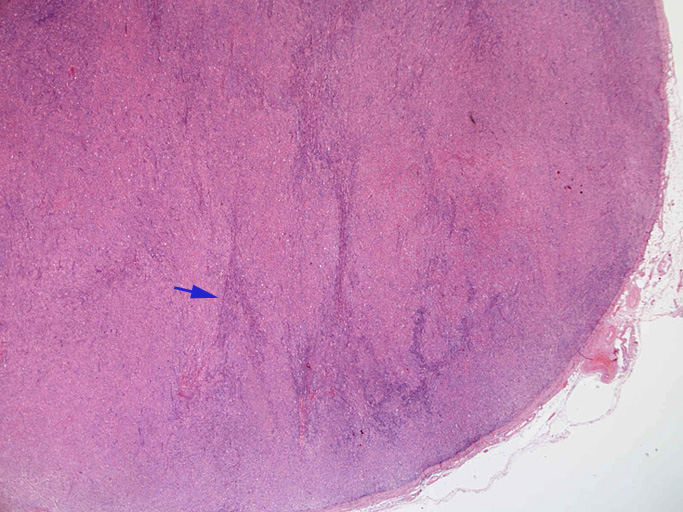

直径17mmの腫大したリンパ節。被膜は軽度線維性肥厚を示す。リンパ節の基本構造は失われ不明瞭な結節様構造が集蔟しているように見える。

光顕および免疫染色所見